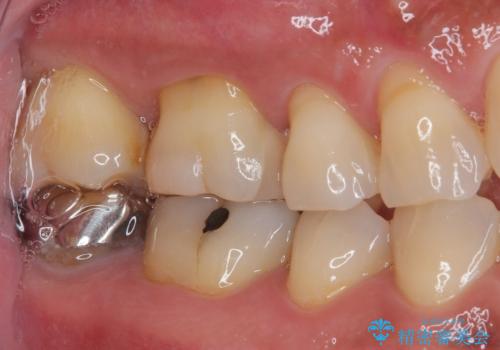

特に異常もなく見た目、噛み合わせともに満足していただけました。

ラバーダム防湿を行い、セラミックの接着をすることで、唾液や血液などの接着阻害因子を排除することができます。

今後はメンテナンスで通ってもらいながら経過を診ていく予定です。